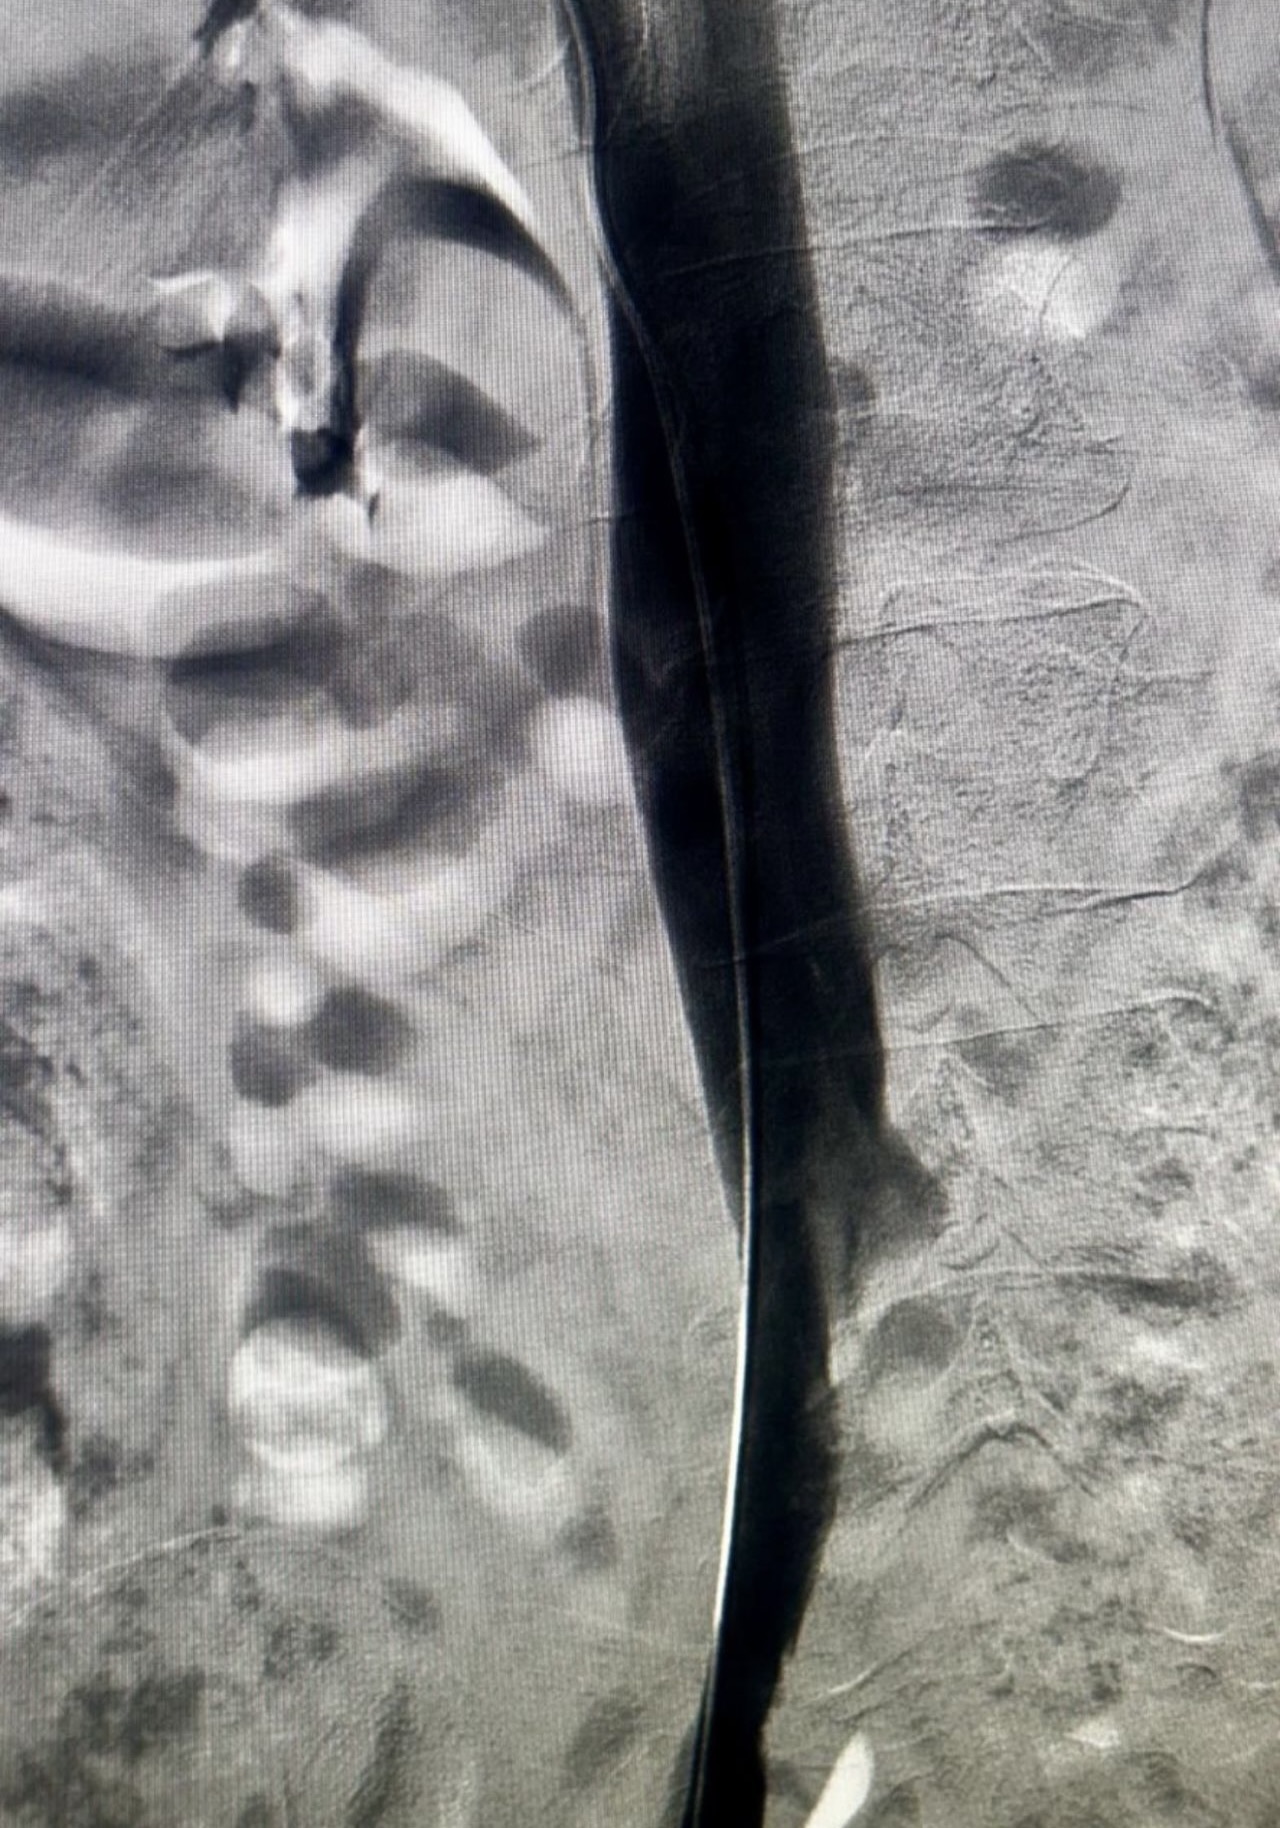

”Rapid Revascularization for Iliofemoral DVT

Acute extensive iliofemoral DVT demands a definitive solution.

The Case: Complete occlusion of the right iliac and femoral veins.

The Procedure:

1. Transpopliteal Access for direct control.

2. Mechanical Thrombectomy using the Penumbra 16 catheter for rapid clot aspiration.

3. Adjunctive Balloon Angioplasty to address underlying venous stenoses and ensure a durable result.

The Outcome: Immediate restoration of flow, resolution of symptoms, and a significant reduction in the risk of Post-Thrombotic Syndrome.

A powerful, minimally invasive approach that changes the patient’s trajectory.”